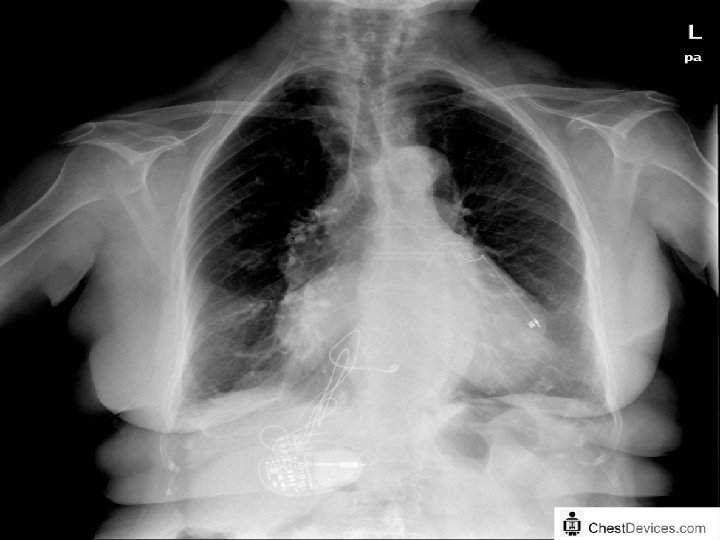

RATIONALE FOR CRT ‘PRESENCE OF BUNDLE BRANCH BLOCK CAN WORSEN HF DUE TO SYSTOLIC DYSFUNCTION BY CAUSING VENTRICULAR DYSSYNCHRONY, THEREBY INDUCING REGIONAL LOADING DISPARITIES AND REDUCING THE EFFICIENCY OF CONTRACTION. A VARIETY OF HEMODYNAMIC BENEFITS FOLLOW THE CORRECTION OF DYSSYNCHRONY WITH CRT. ’

CURRENT GUIDELINES FOR CRT • WITH LVEF <35% NICE, ESC AND ACC GUIDELINES RECOMMEND: • • CRT-D FOR NYHA CLASS 1 TO 3 PATIENTS WITH QRSD >150 MSEC CRT-D FOR CLASS 2 AND 3 PATIENTS WITH LBBB AND QRSD 130 -149 MSEC STAND ALONE CRT-P IN NYHA CLASS 4 PATIENTS WITH ECG CRITERIA AS ABOVE ROLE OF ECHO – DURING WORKUP LIMITED TO LVEF ASSESSMENT. SOME ROLE OF ECHO IN INTRAVENTRICULAR DYSSYNCHRONY ASSESSMENT IN LBBB WITHQRSD 120 -130 MSEC POST IMPLANT – ECHO HAS ROLE IN CRT OPTIMISATION